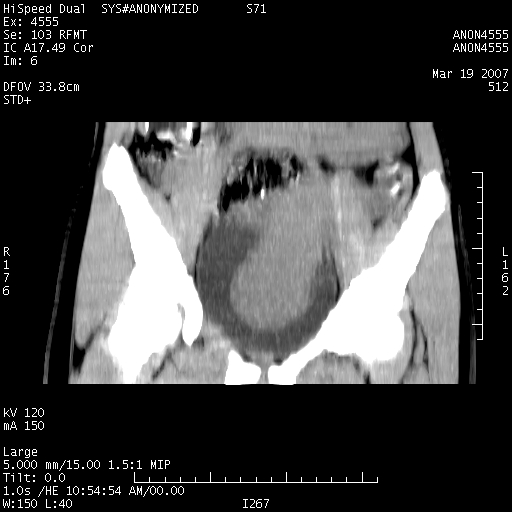

女,14岁,腹痛腹胀月余,患者发育正常,无月经史,检查发现下腹部肿块。患者碘过敏试验阳性。

子宫处见大的软组织肿块,考虑患者女性、14岁无月经,怀疑子宫发育异常

处女膜闭锁,阴道积血。

从矢状位上可见阴道部位明显增粗,内容密度较低,结合患者年龄和临床表现,首先考虑为先天性处女膜闭锁。

处女膜闭锁,阴道、子宫积血。

结合病史考虑处女膜闭锁致阴道、子宫积血。

考虑为先天性处女膜闭锁所致的阴道及子宫积血

子宫内膜异位出血引起的不同部位的宫内膜囊肿可以基本排除

子宫内膜异位主要发生在有分泌功能的子宫及不孕妇女,主要部位在卵巢,当伴发出血时可导致卵巢的宫内膜囊肿,患者常有痛经史.